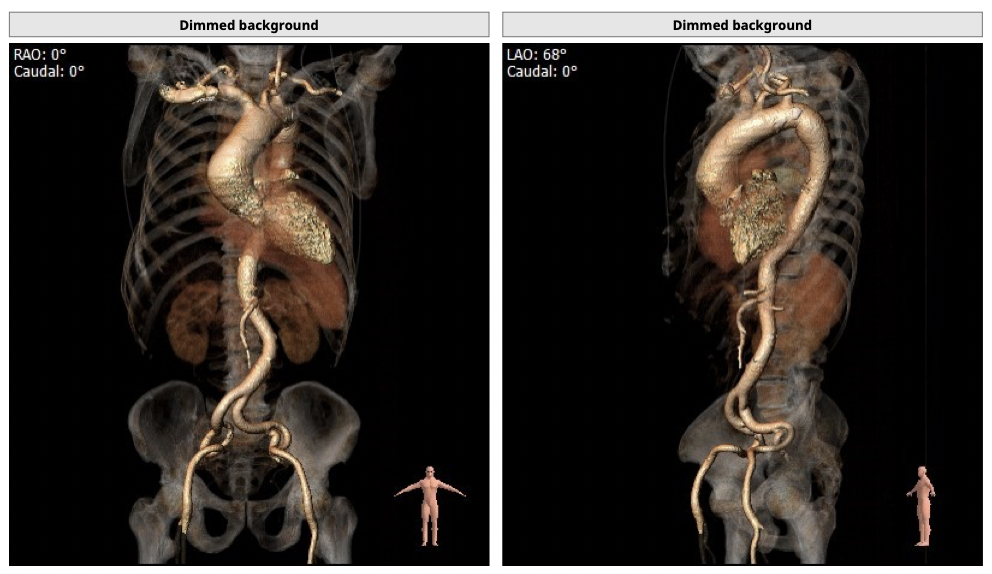

主动脉CT

*升主动脉明显扩张,术中操作需轻柔;

*髂动脉走形迂曲,升主动脉明显扩张,术中操作需轻柔;